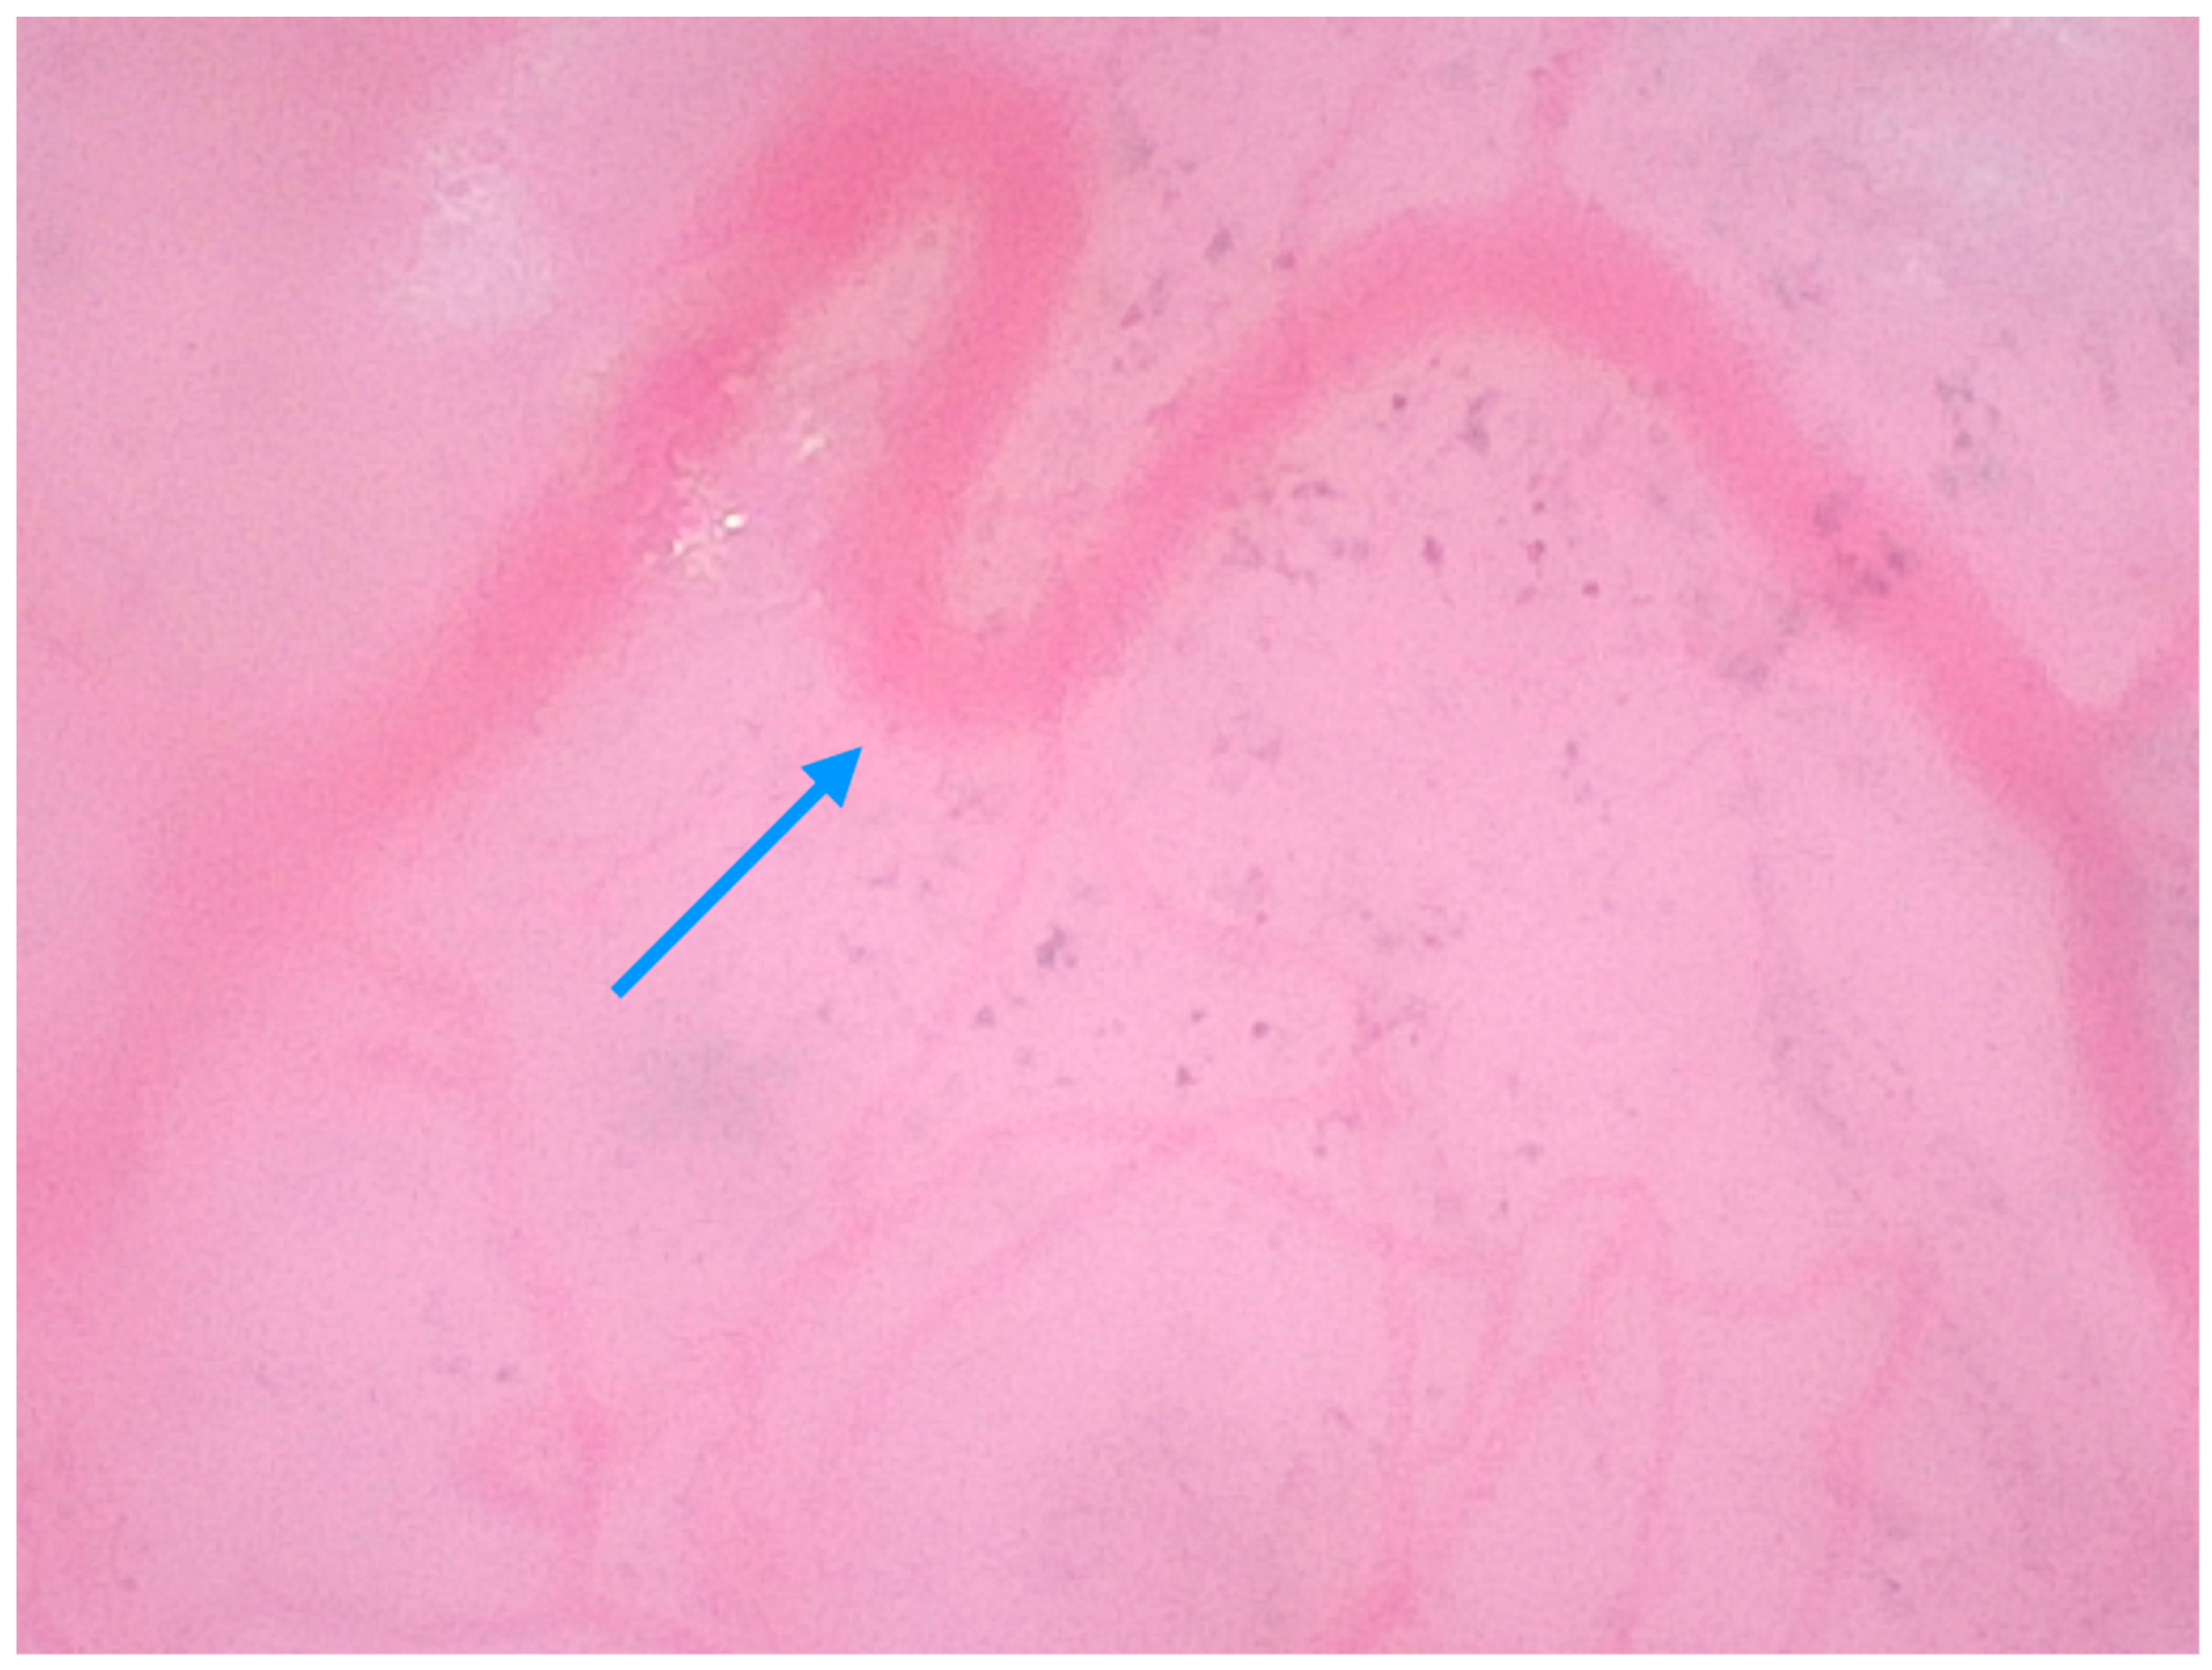

| Pogorzelska-Dyrbuś et al. (2025) [24] | Case series | A 73-year-old female patient with a solar lentigo on her left cheek, and a 55-year-old female patient with lplk on her right arm. | Solar lentigo: Brown-reddish uniform polygonal structures corresponding to keratinocytes that contoured follicular openings, areas of dense arrangement of brown polygonal structures with well-defined borders. Lichen planus-like keratosis: Numerous blue-purple large structures corresponding to melanophages with straight linear vessels. | V |